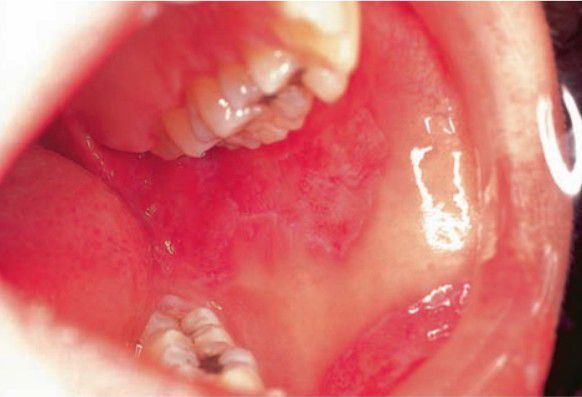

Lupus erythmatosus (oral manifestation)

Usually painful erythematous and ulcerative lesions on buccal mucosa, gingiva, and vermilion; radiating white keratotic areas may surround lesions